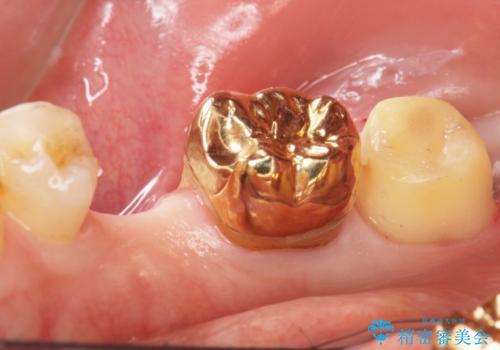

親知らずを抜歯して隣の歯のう蝕を除去し、歯肉の治癒をしっかり待ったのち、患者様のご希望によりゴールド(PGA)クラウンによる補綴を行いました。

右下7:ゴールド(PGA)クラウン